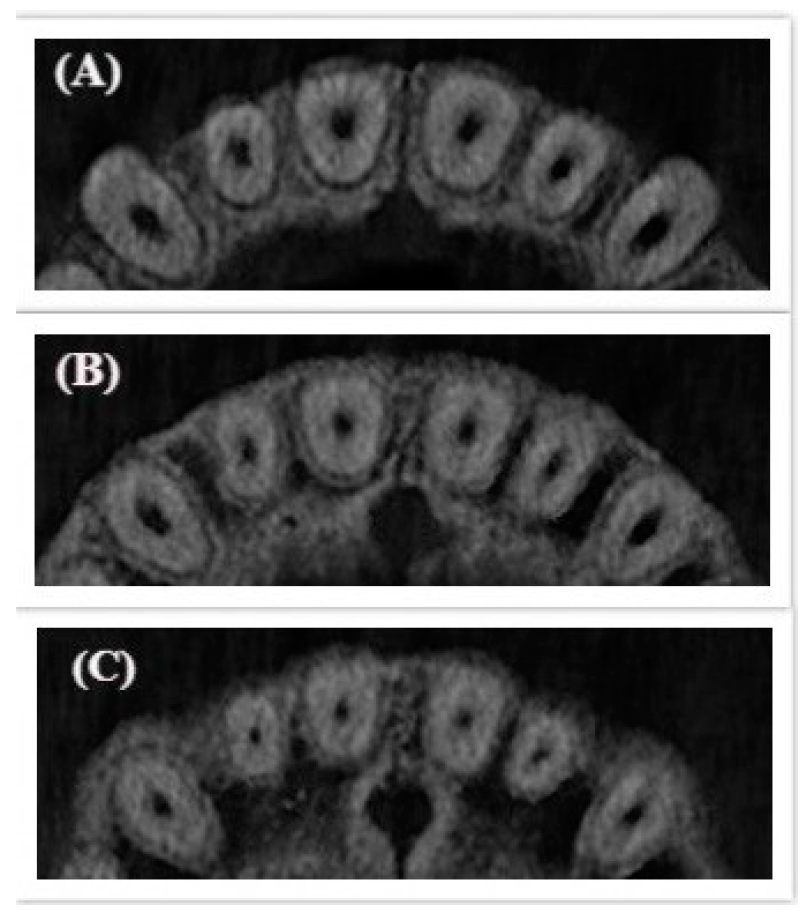

| Type I | Un-changed cross-sectional root canal shape from coronal to apical third |

| Type II | Changed cross-sectional root canal shape in the middle third |

| Type III | Changed cross-sectional root canal shape in the middle and apical thirds |

| Type IV | Changed cross-sectional root canal shape in the apical third |